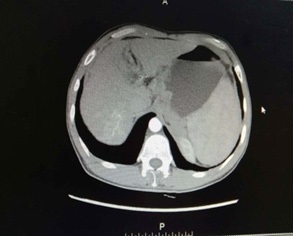

Figure 3: Results of gastroscopy (Gastric antrum placeholder).

The patient, a 55-year-old male, was admitted to the hospital on March 11, 2021 due to “upper abdominal distension, pain and discomfort for more than 1 year, and recurrence for more than 2 months”. More than 1 year ago, the patient had no obvious inducement of upper abdominal distension, pain and discomfort, no acid reflux, heartburn, no nausea, vomiting, no hemesis, melena, no chest pain, chest tightness and other discomfort, no care, no diagnosis and treatment. Before 2 months, the patient’s symptoms were aggravated again, and the symptoms continued to be not relieved, so the emergency department was admitted to our hospital as “abdominal distension cause check”. Previous healthy, smoking and drinking history, no similar patients in the family. Improve relevant examinations after admission, such as: Infectious disease screening: hepatitis B surface antigen (gold standard method) positive (+), HBVDNA: 3.89 x 106 IU/ml, TAP: 128.03 um², liver function:TP: 50.23 g/L ALB: 27.8 g/L, TBIL: 34.8 g/L, DBIL: 15.00 g/L, IBIL: 19.8 g/L, ALT: 27 g/L, AST: 51 g/L, PCHE: 1879 g/L, AFP: 203.8 ng/ml, Color Doppler ultrasonography of chest and abdomen showed that liver cirrhosis was possible, portal vein velocity decreased, liver disease gallbladder, splenomegaly and splenic vein dilation. 256 row chest and upper abdomen CT (plain scan + enhanced): 1. Ground glass shadow of left lung, follow-up and reexamination are recommended; 2. Liver cirrhosis, splenomegaly, esophagogastric fundus and splenic collateral circulation; The abnormal enhancement focus in the right lobe of the liver, considering the high possibility of liver cancer, the remaining small nodule like enhancement in the liver, considering intrahepatic metastasis (Figure 1). 3. Gastric antrum space occupying, considering malignancy, please combine clinical and pathological findings. 3.0 Mr upper abdomen (plain scan + enhancement): 1. Liver cirrhosis with regenerative nodules, splenomegaly, portal hypertension, ascites and collateral circulation; 2. Abnormal signal of right posterior lobe of liver (Figure 2). Considering malignancy, please combine clinical and AFP examination. Gastroscopy showed: 1. Esophageal gastric fundus varices (severe); 2. Gastric antrum space occupying: Ca? (Figure 3); Gastric antrum pathology (HE staining Figure 4) results: (gastric antrum) adenocarcinoma. Liver puncture pathology (immunohistochemical (Figure 5) diagnosis: (liver puncture) combined with immunohistochemical results, it is consistent with hepatocellular carcinoma. Immunohistochemistry: CerbB2 (0), CK (+), HEPA (partial +), glypican (+), CD (small amount +), CD34 (blood sinus +), CK7 (-), CK8 (+), CK19 (-), CDX2 (-), Ki67 (50% +), GS (+), CK20 (-). Physical examination: Body temperature was 37OC, pulse was 78 beats/ min, respiration was 20 beats/min, blood pressure was 120/70 MHg, skin and mucosa of the whole body were mildly yellow, no rash, bleeding spots, liver palm or spider nevus, superficial lymph nodes were not touched and enlarged, and no obvious abnormalities were found in head, neck, heart and lungs during physical examination. Abdominal distention, soft abdomen, no obvious tenderness, rebound pain and muscle tension in the abdomen, liver, spleen and ribs are not touched, negative mobility dullness, bowel sounds are normal. The patient refused interventional therapy, asked for oral chemotherapy and was discharged after her symptoms improved.